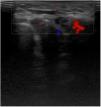

Ultrasound studyAfter an ultrasound study with a 22Hz probe, small thickenings of the subcutaneous cellular tissue were seen, partially defined, superficial, without invasion of deep planes, or notable findings on the color Doppler ultrasound (Fig. 2).